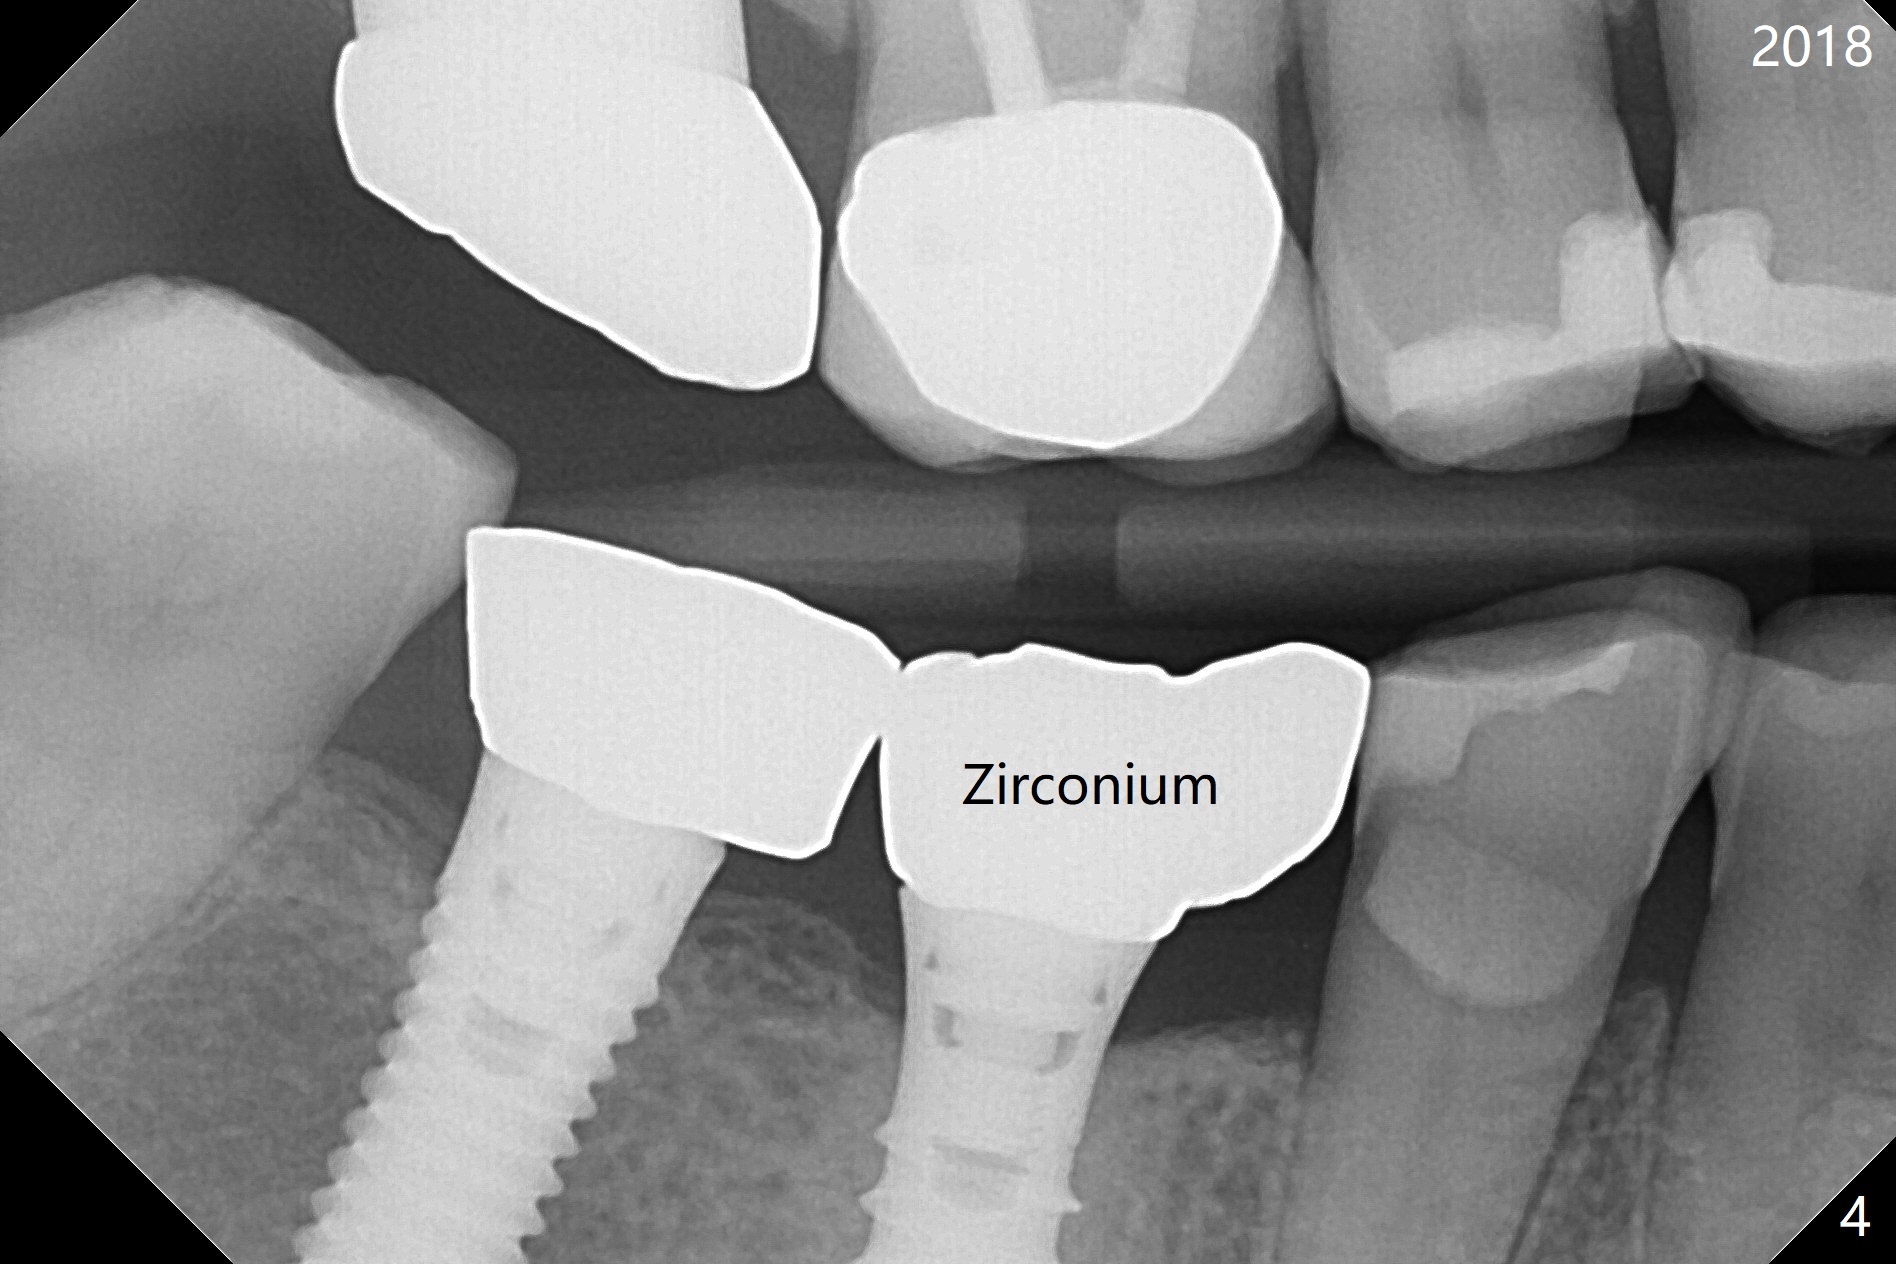

A 50-year-old woman is a bruxer. There are 3 PFM crowns at #3, 30 and 31 (Fig.1). A full metal crown is changed at #31 because of porcelain chip 3 years later (Fig.2). A Zirconium crown is fabricated at #2 after tooth fracture; porcelain chips at #30 and the PFM crown is removed (Fig.3) for Zirconium one (Fig.4). It appears that the weakest link lies between two materials (porcelain and metal of PFM crown) under heavy occlusion and when the implant has no flexible mechanism (periodontal ligament). Either full metal crown or Zirconium one is a suitable crown material for bruxer. Note the dense bone around the implant at #30 (Fig.4 (bruxism)).